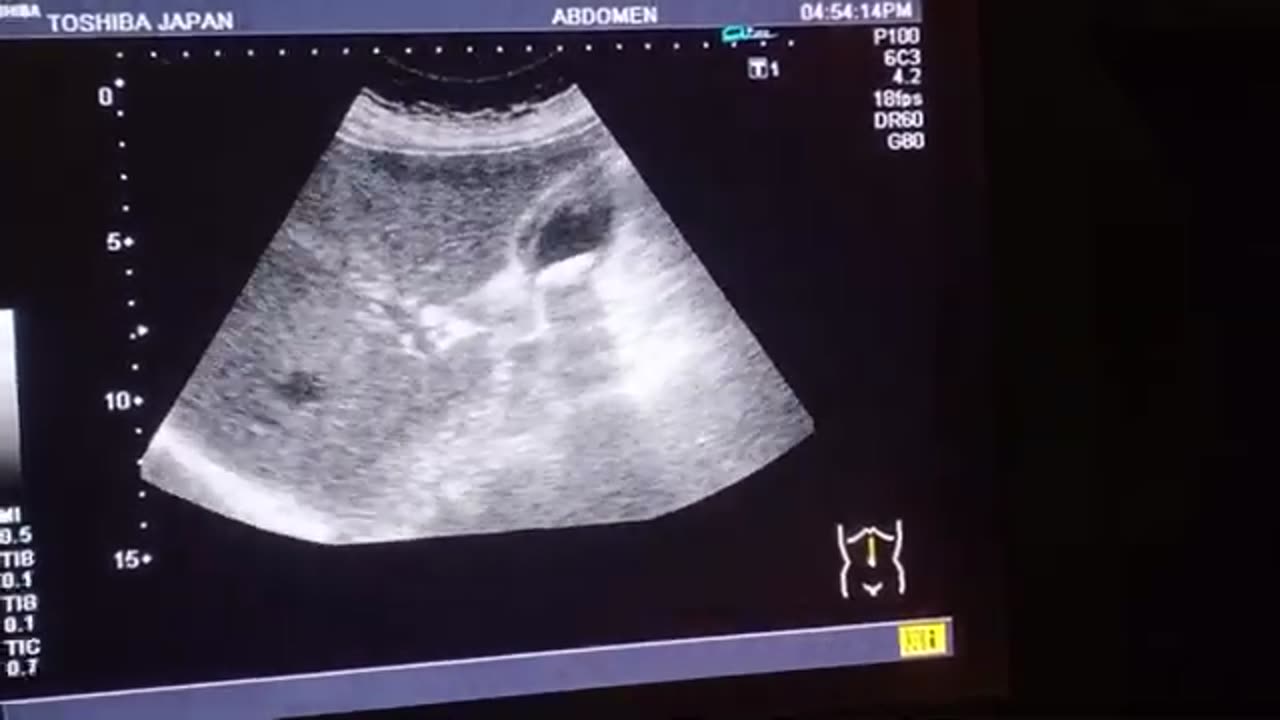

Gallstones With Thick Walled Gallbladder l With Heart Disease l Cholecystitis l